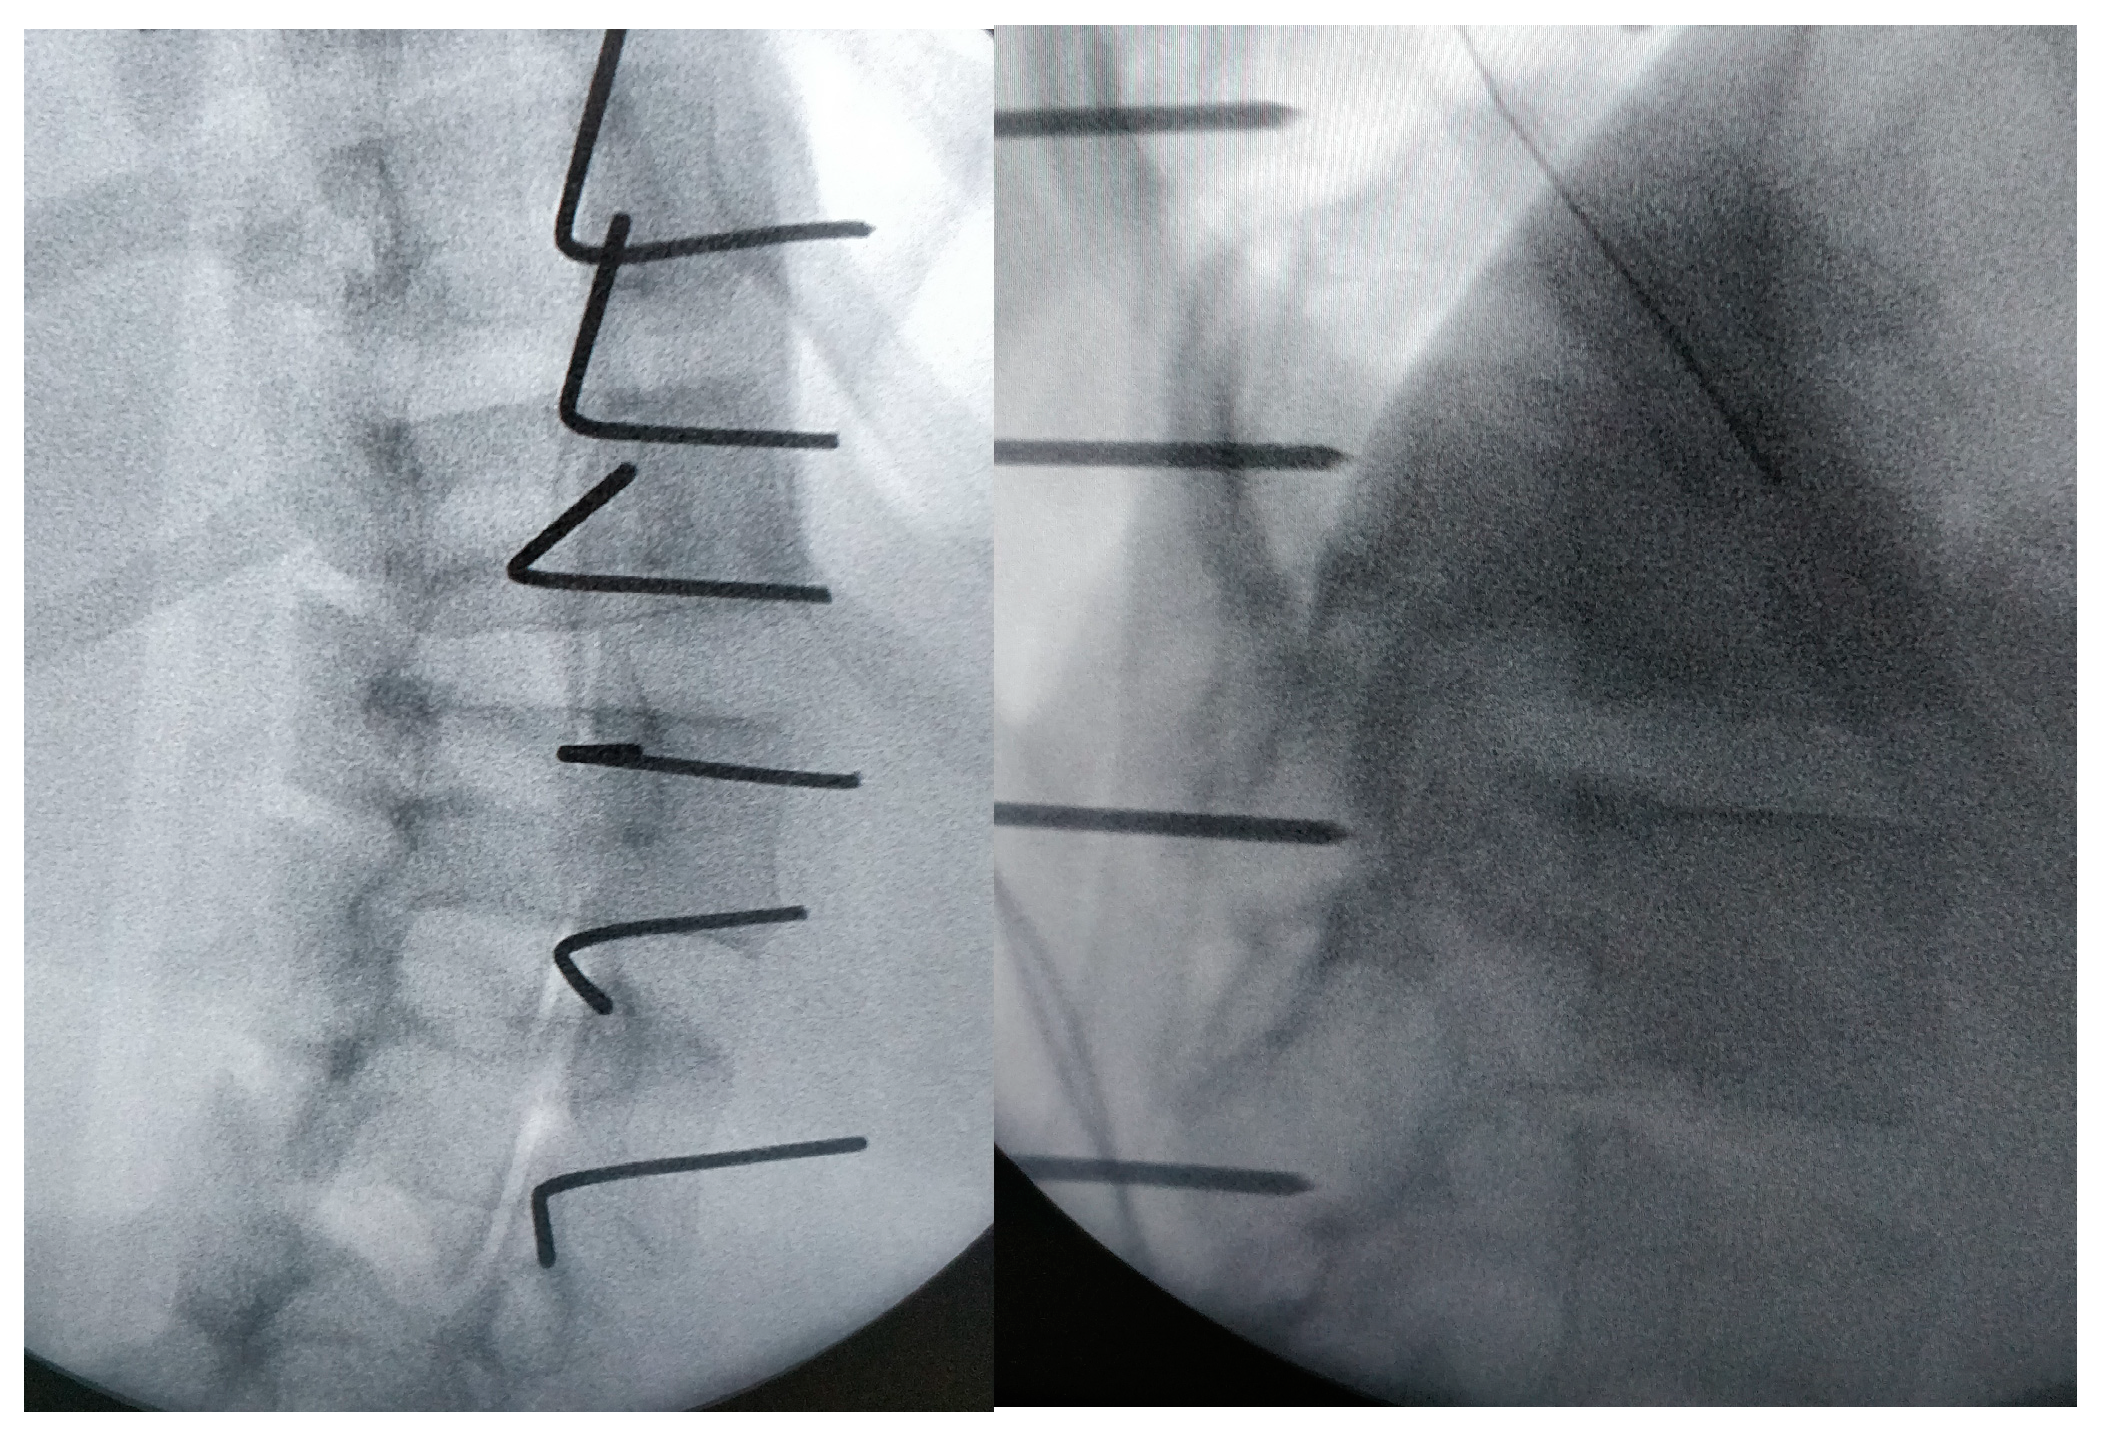

This makes it possible to identify the transverse process and joint of each vertebra. K wire is stuck to the theoretical entry point of the screws at each level under fluoroscopy (Figure 3 and Figure 4); note they are bent at 90° to better identify their position on the X-ray.

View of the pins: they are stuck to the theoretical entry point and bent for a better identification on the X-ray.

Frontal and sagittal view on the X-ray: it allows the perfect entry point and the right direction of the screws to be checked.

Then, if possible, a three-dimensional acquisition is made to evaluate the ideal path of the screws for each level. A Pediguard® is used to enter the pedicles safely and avoid the wrong way as much as possible. With a palpator, the presence of bone all around the tunnel is checked, allowing the length to also be measured. The screws (diameter 5.5 to 6.5 mm) are then put in place in the pedicles. Of course, for this step, surgeons should use the same technique they usually use for pedicle screws. Then, new fluoroscopy is performed to assess their perfect position (Figure 5).

Frontal view of the screws; to check their good position, a sagittal view is also performed.